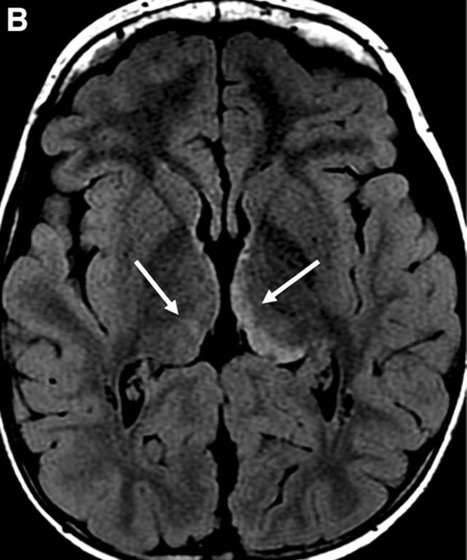

c. Lipomatose encéphalocraniocutanée (ECCL): peau, yeux, SNC)

ECCL: